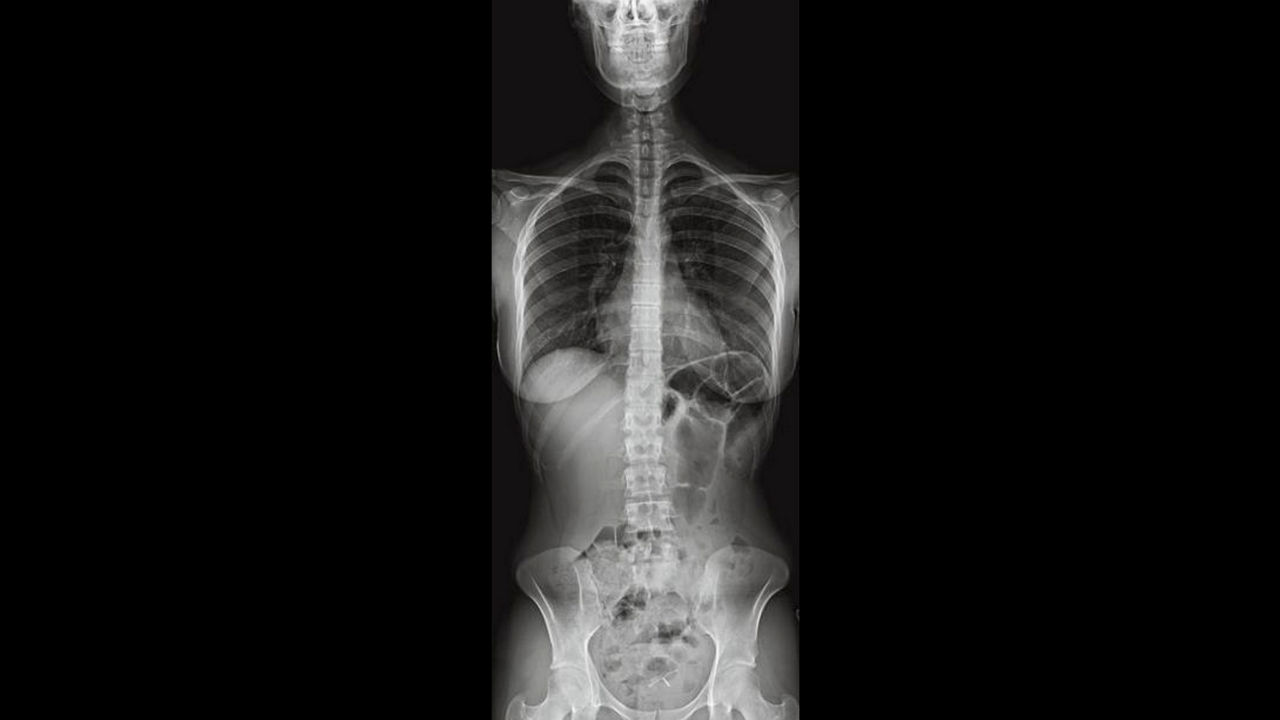

Dual Energy Subtraction

Helps eliminate obstructions from overlying bones while providing additional information.